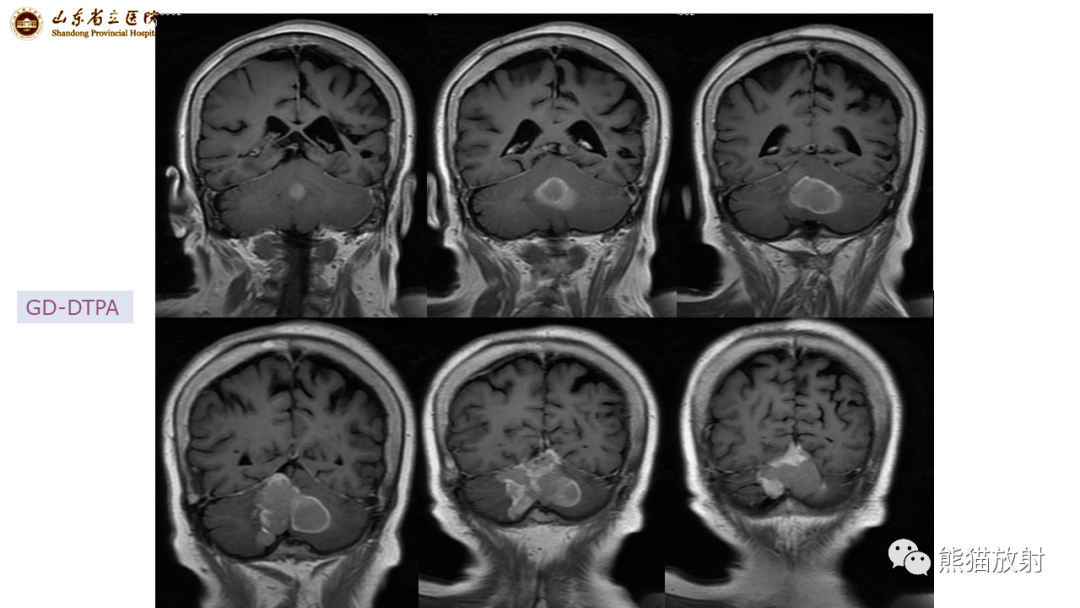

【病例】炎性肉芽肿并脓肿形成 & 成熟性囊性畸胎瘤-3